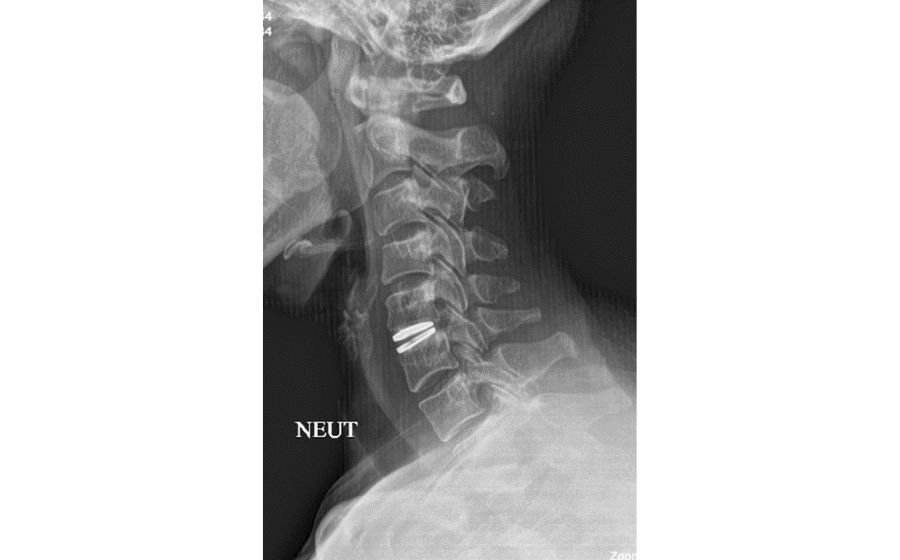

Cervical Disc Replacement (Cervical ADR)

Cervical disc replacement is an advanced alternative to fusion for select patients with disc herniation or degeneration in the neck. Instead of fusing the bones, the damaged disc is removed and replaced with an artificial disc that preserves natural neck motion. This maintains mobility while relieving pressure on the nerves and spinal cord. ADR is designed to reduce pain, improve function, and lower the risk of adjacent level degeneration in the long term.